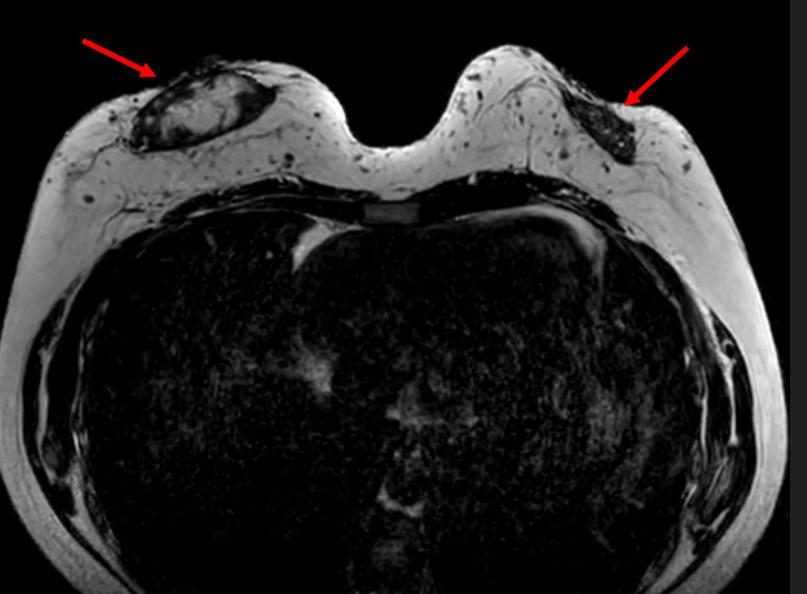

腋下MR影像显示双侧呈球形肿块,在T1WI上表现为低信号。在T1WI对比增强脂肪饱和影像中,可见腋下肿块呈异质性明显强化,伴有点状脂肪区域(图6、7)。

ccb86a91f6c48188bcd8ee7993601a4b.jpgf7ef49ccf18c7a0e3c51ddb77209d20f.jpg